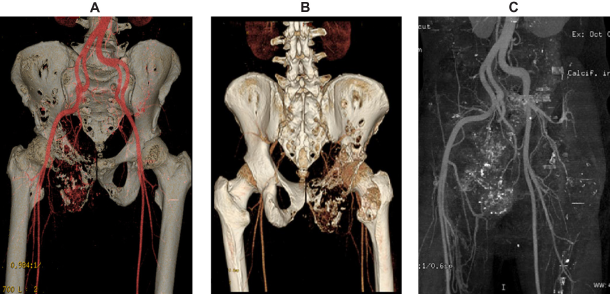

The results of imaging tests can be viewed as markers for early detection. Because they involve a subjective component, the method of evaluation differs from that of circulating markers. Advances in imaging are transforming our understanding of tumor angiogenesis of osteosarcoma3–5 (Fig. 2). Vascular imaging makes it possible to quantify the number and spacing of blood vessels, measure blood flow and vascular permeability, and analyze cellular and molecular abnormalities in blood vessel walls.6,7 An examples of an imaging marker for the early detection of osteosarcoma is low-dose computed tomography angiography (CTA). Imaging angiogenesis in osteosarcoma is useful for clarificying the structural and functional abnormalities of angiogenic blood vessels.

Example of osteosarcoma reconstruction by volume-rendered 3D CTA image in anatomic orientation. A) This volume-rendered 3D CTA image, in anteroposterior projection, demonstrates the vascularity of the pelvic region, especially near the lytic lesion of the right pelvic bones. B) This volume-rendered 3D CTA image, in posteroanterior projection, demonstrates the vascularity of the pelvic region, especially near the lytic lesion of the right pelvic bones. C) Reconstruction of osteosarcoma by 3D CTA with bone sustraction showing the arterial vascularity of pelvic region.